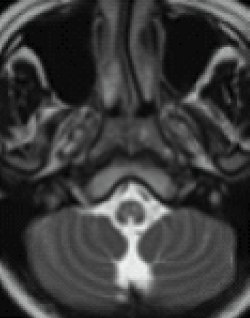

An additional imaging pattern characterized by bilateral symmetric hyperintensity on T2-weighted imaging involving the central inferior olivary nucleus, the pyramids, and the cuneate and gracile fascicles, with sparing of the peripheral inferior olivary nucleus and inferior peduncle (termed the “chipmunk sign”), is a common feature in people with Alexander disease regardless of age of onset.62